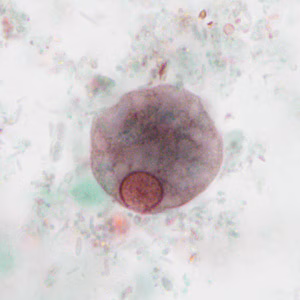

Stool specimens were collected from an asymptomatic 10-year-old boy from Panama as part of a refugee screening program. The stool was collected in 10% formalin and zinc PVA (Zn-PVA) and sent to the county health department for routine ova-and-parasite (O&P) examination. Figures A – I show what was observed at 1000x magnification with oil on a trichrome-stained slide made from stool preserved in Zn-PVA. Objects in Figures A and G measured approximately 10 micrometers; all other objects of interest ranged from 17-25 micrometers. Figures C – E show different focal planes of the same object of interest to highlight internal structures. What is your diagnosis? Based on what criteria?

Figure B